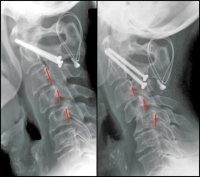

Abbildung 3: Seitliche Röntgenverlaufskontrolle einer subaxialen Subluxation nach 2-jährigem Verlauf. Zunehmendes Treppenstufenphänomen der Segmente HW 3/4 und 4/5. Zustand nach transartikulärer Verschraubung von HWK 1/2 4 Jahre zuvor.

Keywords: Röntgensubaxialen Subluxationtransartikulärer VerschraubungTreppenstufenphänomenVerlaufskontrolle